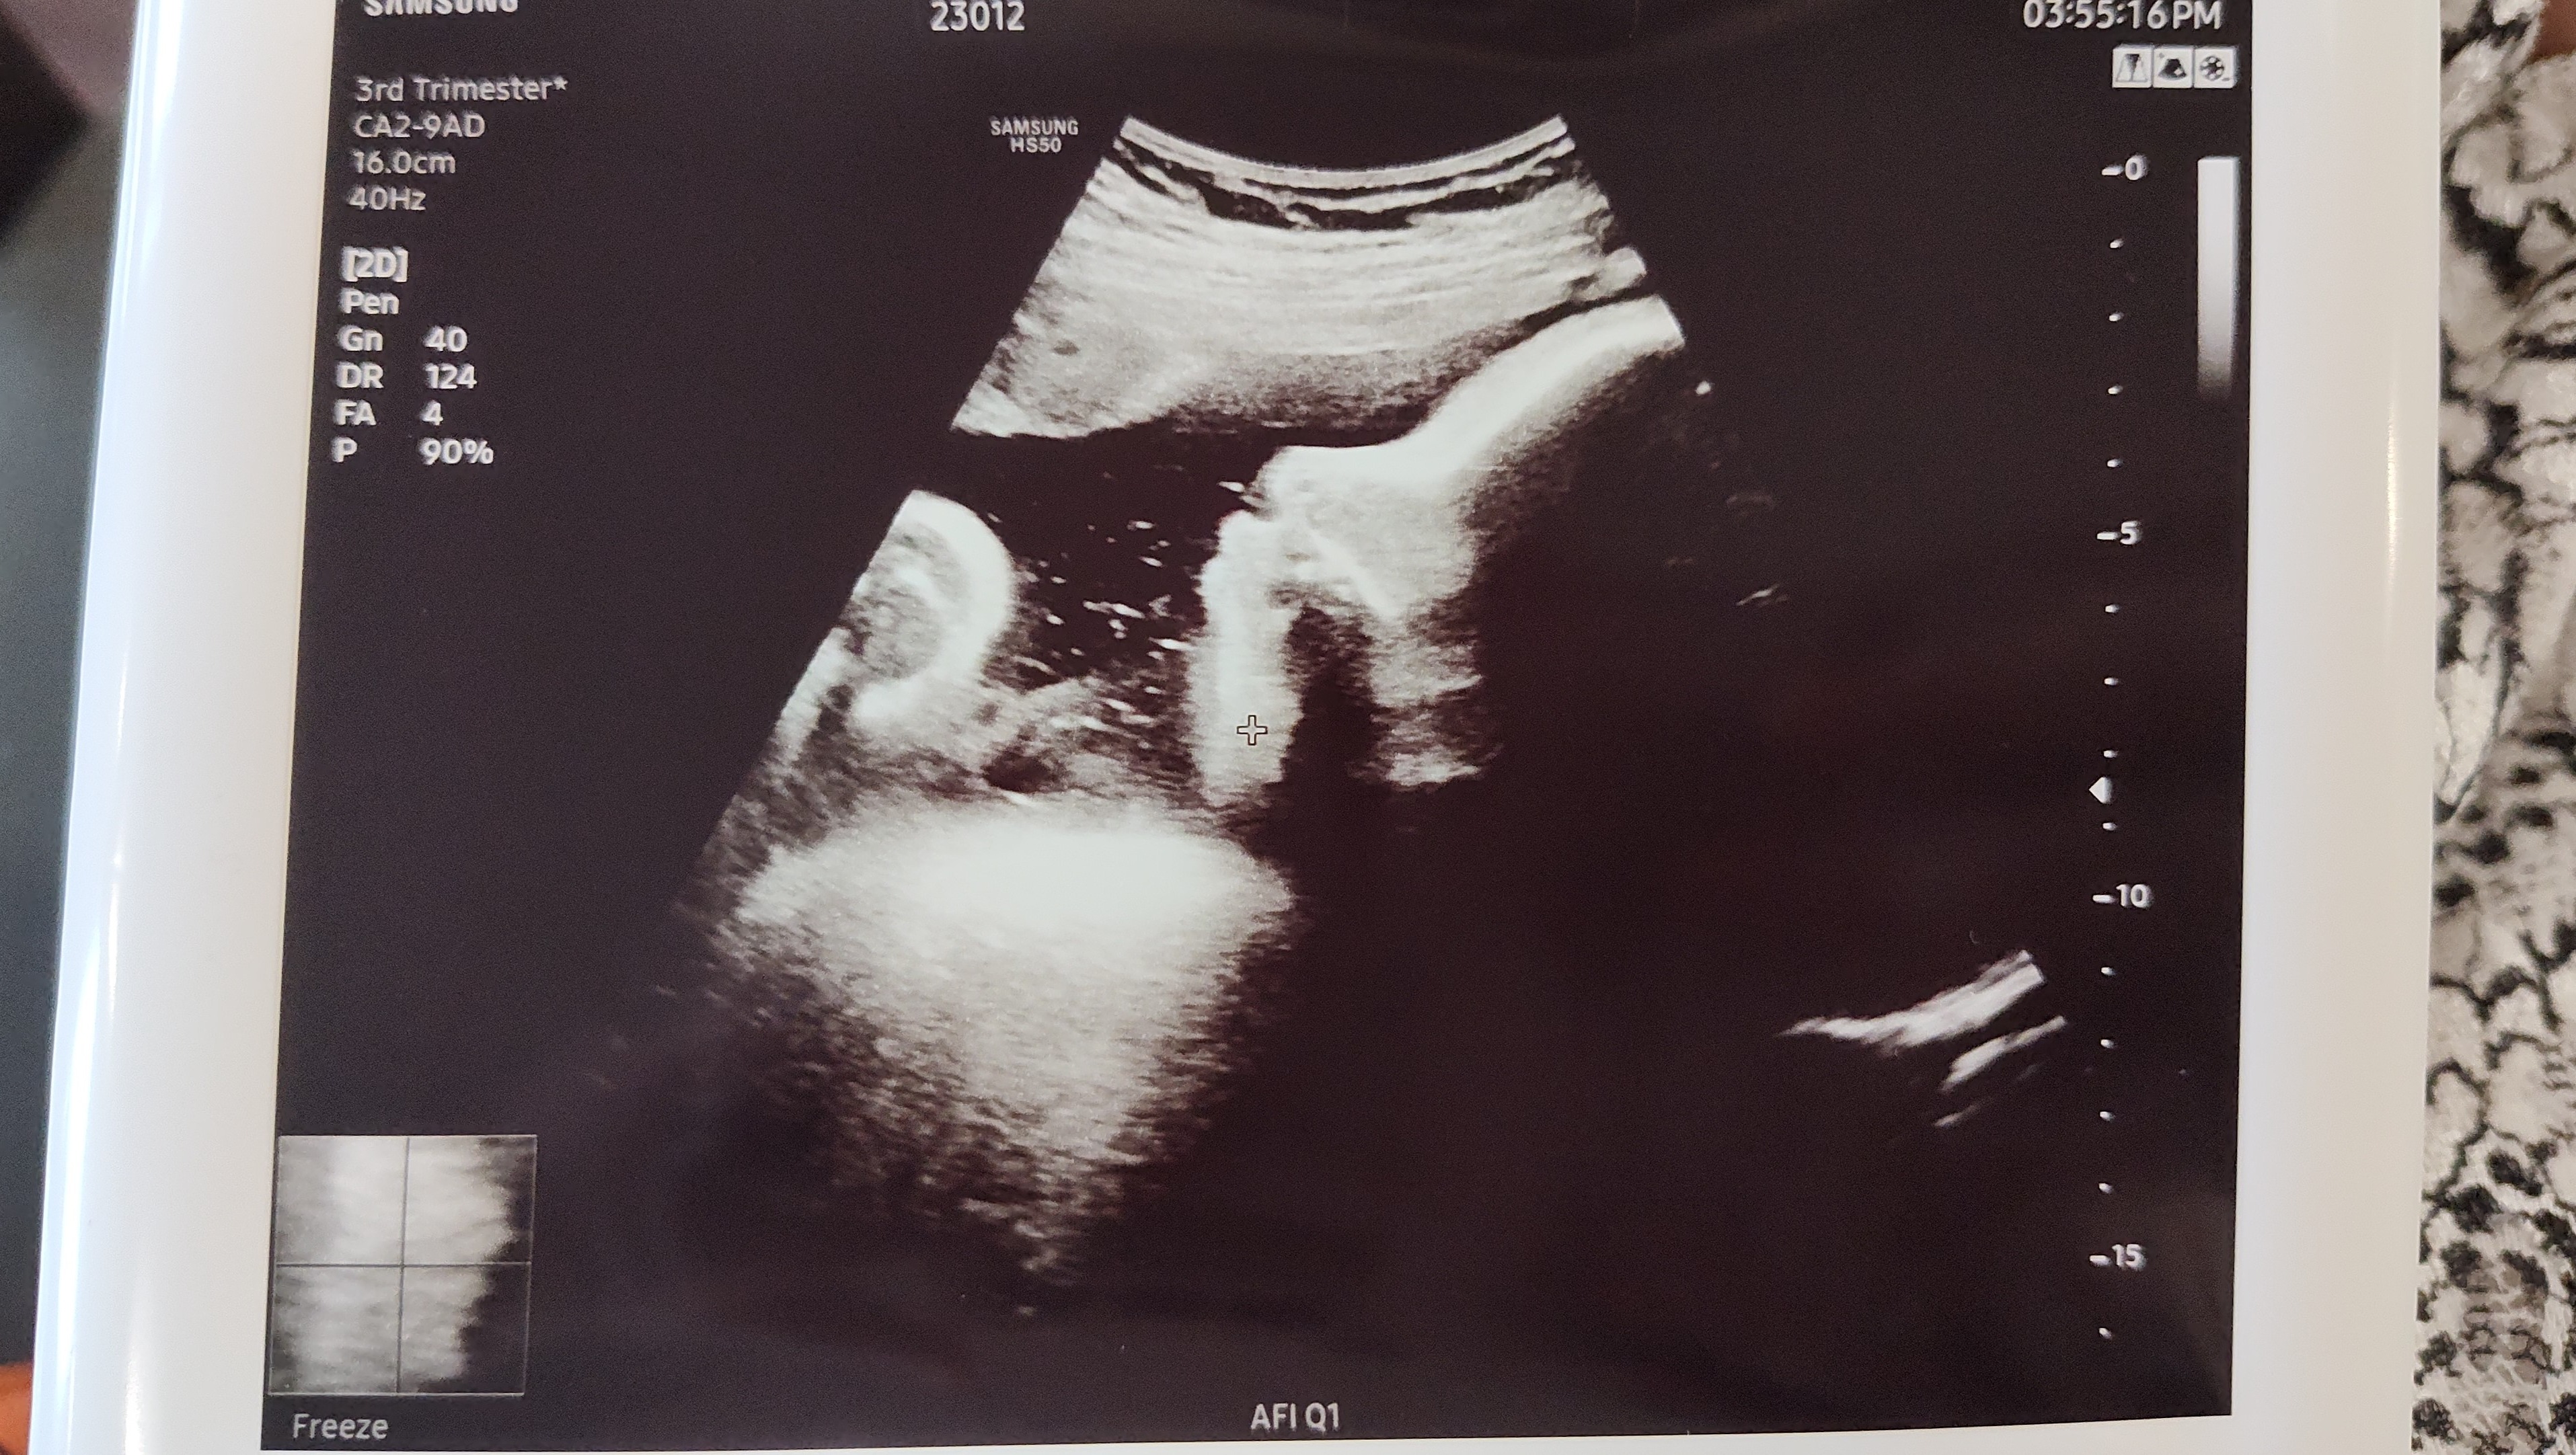

The birth mother was a little over eight months pregnant when we first met her. By late April, she was asked by her doctor to come in for a check-up on the baby twice a week every week. In the interest of taking care of her and our son, Jonah and I would go pick her and her boyfriend up and take them to the doctor's appointment. These trips became our normal weekly routine every Monday and Friday for six weeks, while continuing to work. We would also treat them to a meal while we were there to continue getting to know each other. The time spent in our car alone, not counting time at the doctor's appointment or time visiting with them, totaled 11 hours and 10 minutes. Regularly resulting in 16-to-17-hour long days of travel. Jonah and I were dedicated to our son-to-be.